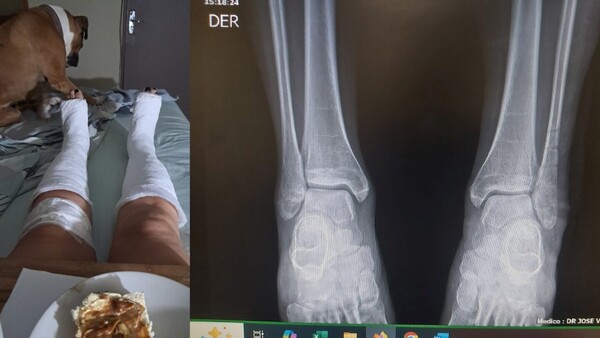

Doña se fracturó las dos piernas al caer en un bache

Ocurrió en diciembre, pero el bache sigue ahí, por lo que decidió hacer público para ver si la Muni de Asunción se digna a arreglar. ...[Leer más]